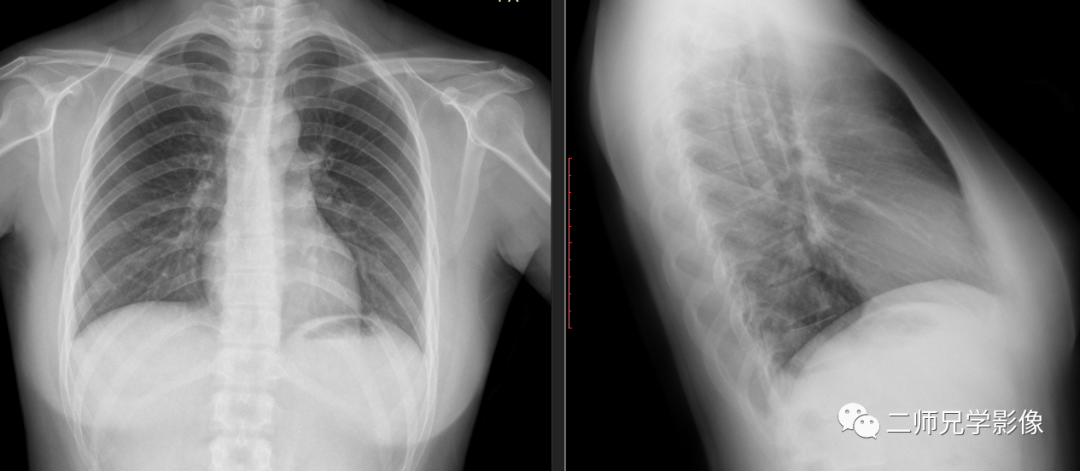

图七:拍摄肺部时,从不同的位置拍摄出不同的肺部影像

以上前五幅图片(图一至图五)就是从不同角度去拍摄不同物体,显示出不同的影像。同样,我们放射科拍片时也是一样的,同一个身体部位,从不同角度去拍摄,就会显示出不同的影像(图六图七)。